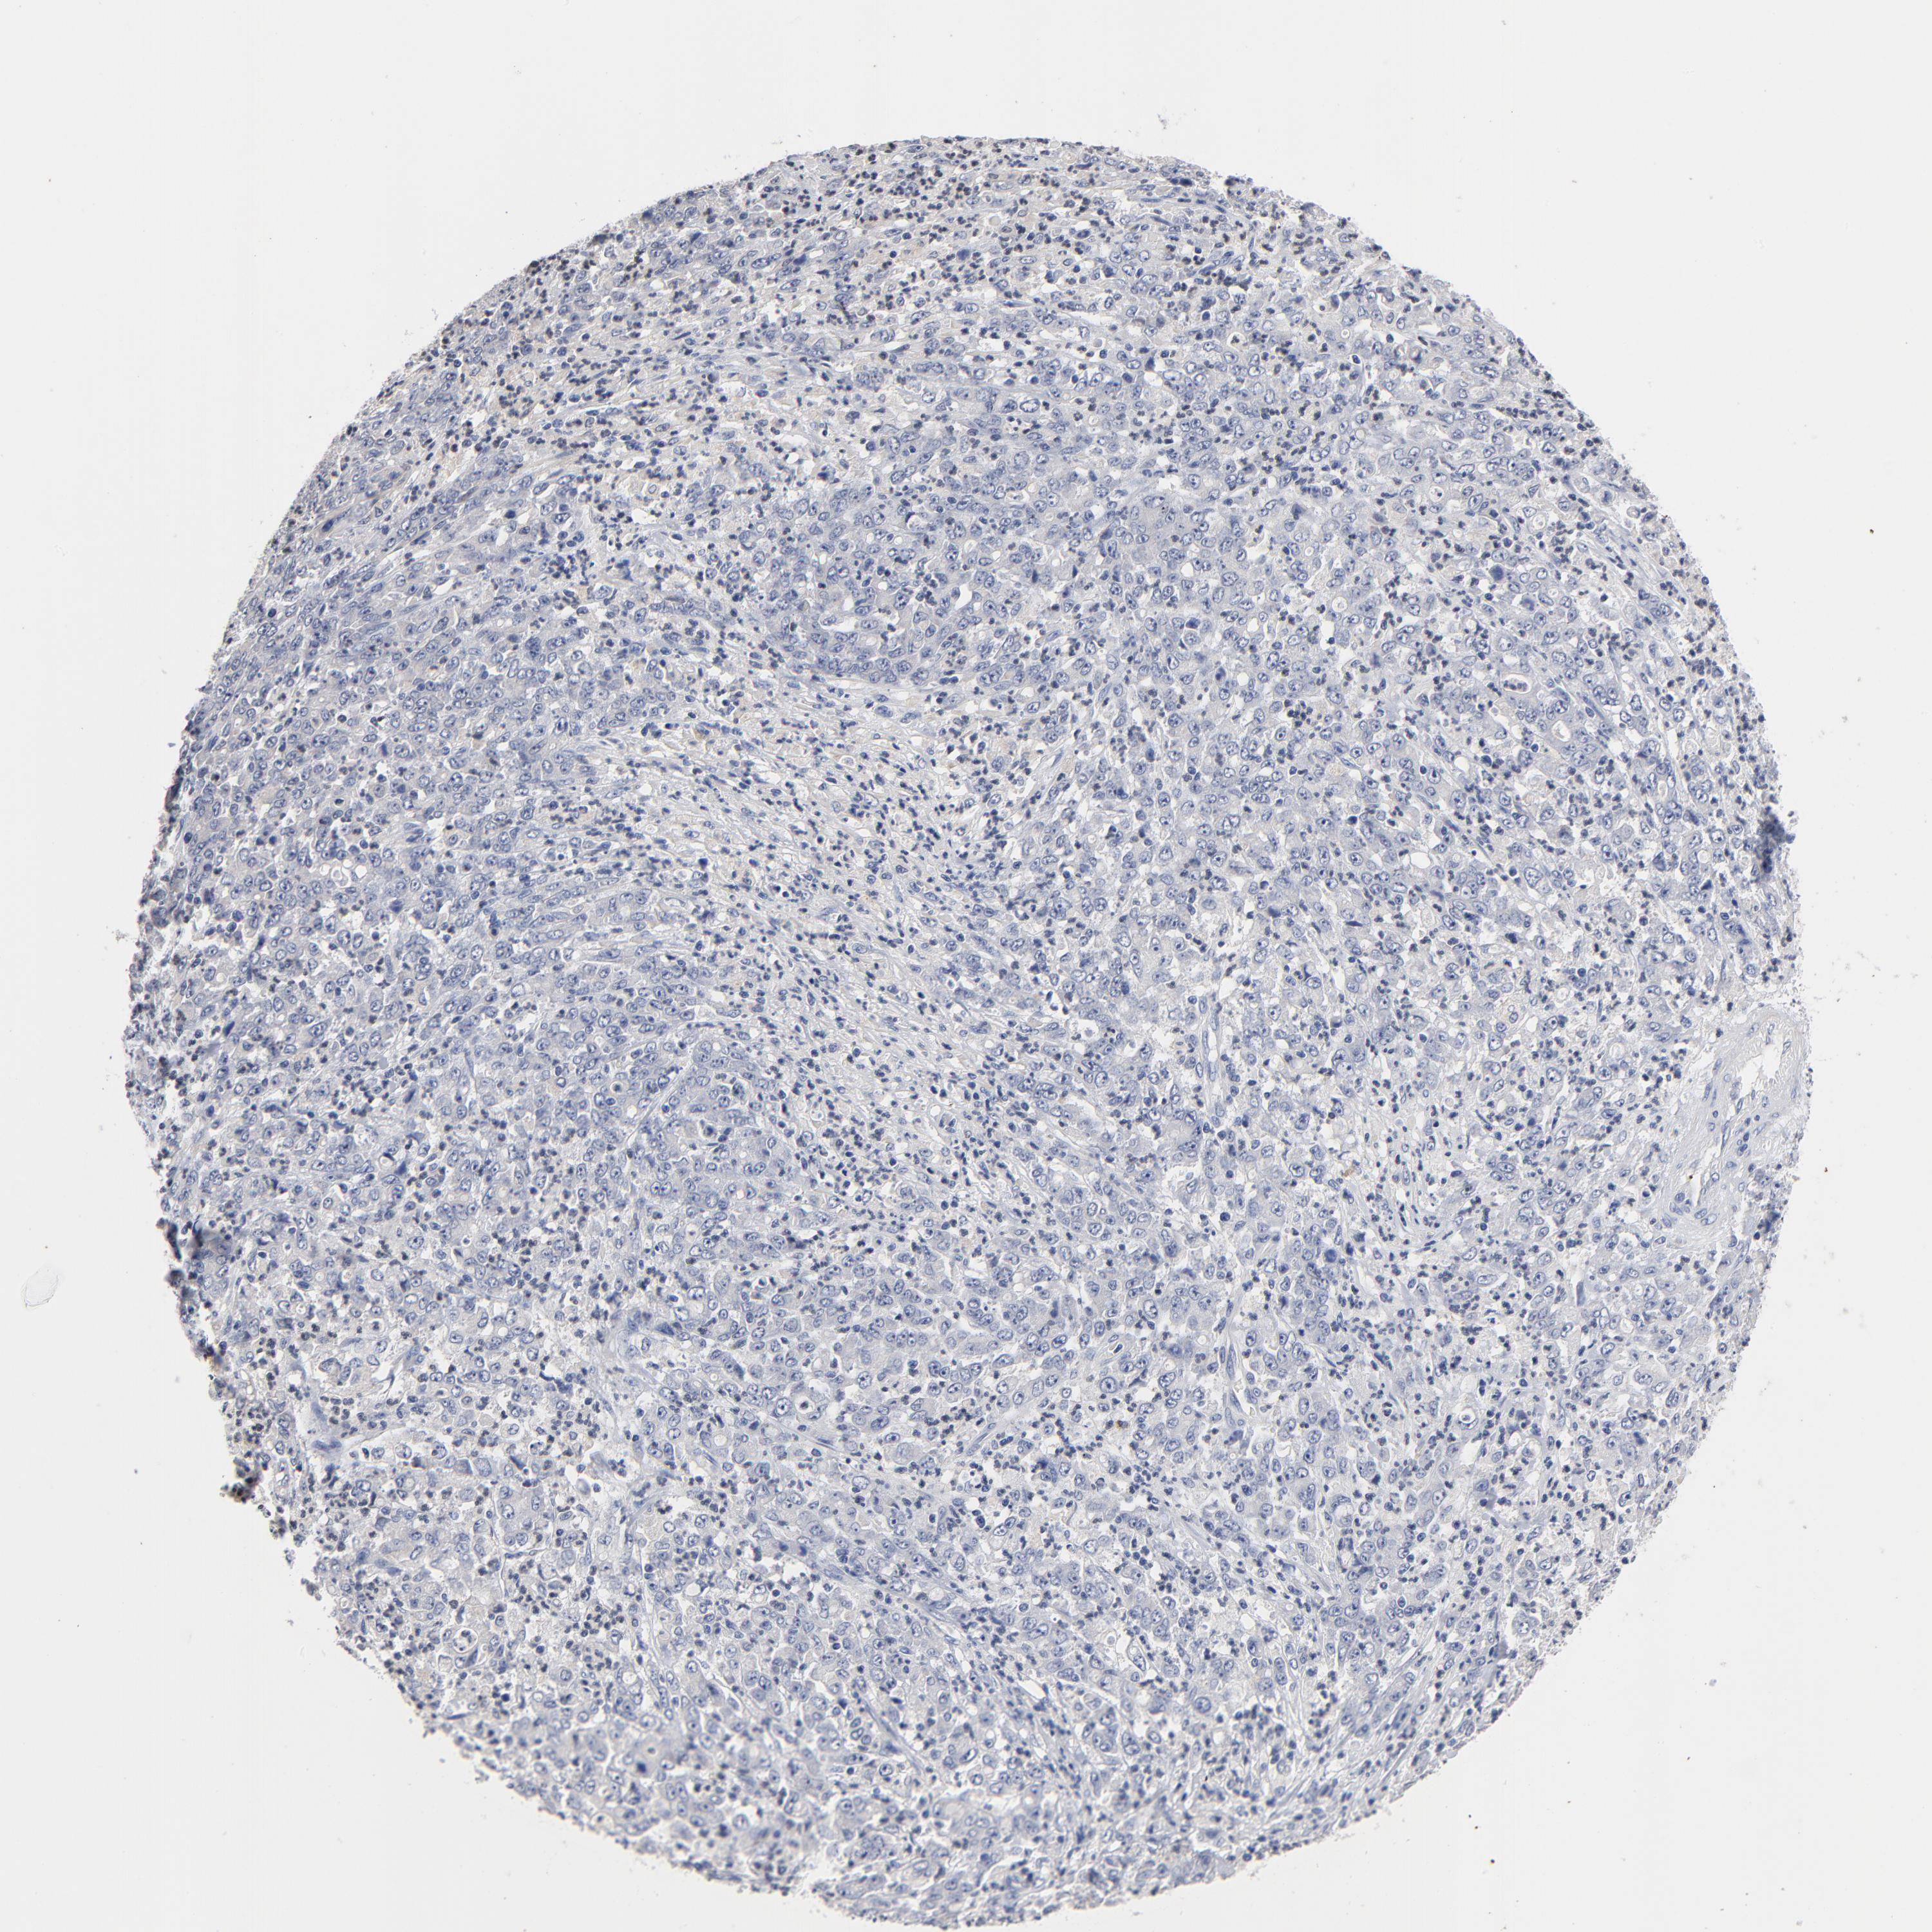

STOMACH CANCER - Protein expressioni

A mouse-over function shows sample information and annotation data. Click on an image to view it in a full screen mode. Samples can be filtered based on level of antibody staining by selecting one or several of the following categories: high, medium, low and not detected. The assay and annotation is described here.

Note that samples used for immunohistochemistry by the Human Protein Atlas do not correspond to samples in the TCGA dataset.

Antibody stainingi

Antibody staining in the annotated cell types in the current human tissue is reported as not detected, low, medium, or high, based on conventional immunohistochemistry profiling in selected tissues. This score is based on the combination of the staining intensity and fraction of stained cells.

Each image is clickable and will lead to virtual microscopy that enables deeper exploration of all samples and also displays staining intensity scores, fraction scores and subcellular localization as well as patient and tissue information for each sample.

Antibody HPA002911

Staining

High

Medium

Low

Not detected

Intensity

Strong

Moderate

Weak

Negative

Quantity

>75%

75%-25%

<25%

None

Location

Nuclear

Cytoplasmic/membranous

Cytoplasmic/membranous,nuclear

Adenocarcinoma, NOS